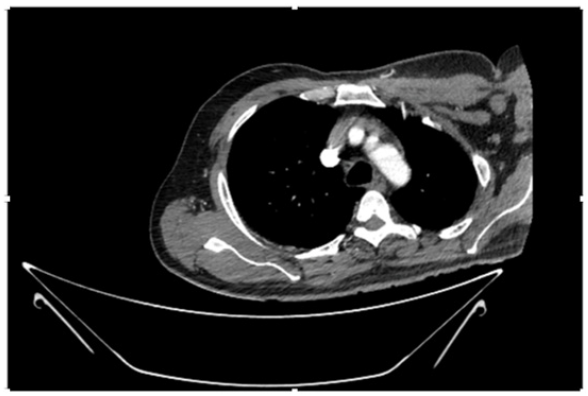

55-years-old chronic smoker had acute, severe pain in the right upper limb for one week; it was cold upto mid arm with skin discoloration. He also noticed numbness and weakness of movement of elbow joint. He underwent below elbow amputation in February 2023 for acute ischemia of left upper limb. He was a current chronic smoker; 15 pack year. General condition was weak; temperature was normal; blood pressure was 100/60mmHg; heart rate was 92/minutes with sinus rhythm; SpO2 was 97% on air; heart was normal. In lower extremities, all peripheral pulses were intact. Local Examination of right upper limb revealed as follows: tenderness; coldness; discoloration; decreased motor function and sensory modalities. Axillary, brachial and radial pulses were not palpable. Hand-held Doppler failed to detect any signal in arterial system; therefore, we arranged for emergency embolectomy. complete occlusion of right upper limb arterial system Full blood count showed high hemoglobin (14.6gm%); normal total WBC and platelet count. Coagulation profile was normal. Parenteral unfractionated heparin, antibiotics, tramadol, proton-pump inhibitors, anti-platelets and HMG CoA reductase inhibitors were given. Doppler ultrasound demonstrated complete occlusion of right upper limb arterial system. CT Angiogram illustrated occlusion of subclavian artery downwards on both sides. Figures 1-14 shows complete occlusion of right subclavian artery without collaterals. On Day ‘2’ of admission, the patient passed black tarry stool for 3 times. However, the vital signs were stable; blood pressure was 100/60mmHg; heart rate was 92/min; SpO2 was 97% on air; the abdomen was soft and not tender. Above elbow amputation was done on Day ‘2’ of admission. Intra-operative findings were as follows: (1) no active bleeding at brachial artery; (2) thrombosis along brachial artery; (3) muscle color and consistency were not healthy.

Figure 4: CT Angiogram at neck showing normal brachio-cephalic trunk, common carotid artery, and narrow right subclavian artery.

Figure 5: CT Angiogram at neck showing normal brachio-cephalic trunk, common carotid artery, and narrow right subclavian artery.

Figure 6: CT Angiogram at neck showing brachio-cephalic trunk, common carotid artery and narrow right subclavian artery.

Figure 7: CT Angiogram at neck showing brachio-cephalic trunk, common carotid artery and narrow right subclavian artery.